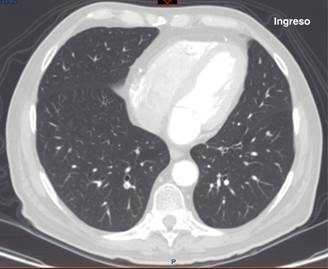

Se describe un caso de SIRPA de evolución fulminante, que se deja apreciar a través de los dramáticos cambios radiológicos que experimentó en corto tiempo. Se trató de un hombre de 69 años previamente sano, que llegó referido de otro hospital por dolor abdominal inespecífico, cambios en sus hábitos intestinales y un cuadro de oclusión intestinal que resultó corresponder a un adenocarcinoma del colon moderadamente diferenciado, invasor, ulcerado; en el postoperatorio inmediato de una hemicolectomía izquierda desarrolló un choque séptico severo refractario al manejo convencional en terapia intensiva, que evolucionó adversa y rápidamente hacia la falla orgánica múltiple (FOM). Es particularmente llamativo el SIRPA grave con el que cursó y que a pesar de maniobras de protección pulmonar, titulación del mejor nivel de PEEP, con manejo hemodinámico avanzado y prono, lo condujo precipitadamente a la muerte. La Figura 1 muestra la radiografía de tórax a su llegada a urgencias, prácticamente normal; esto, como se sabe, puede ocurrir en la fase más temprana del SIRPA, aunque rara vez se documente.6 La Figura 2 pertenece a un corte axial a nivel del tercio inferior del tórax; se puede apreciar parénquima pulmonar de características normales al ingreso al hospital. Se descartaron enfermedad por tromboembolismo venoso y otros procesos intratorácicos, que hacen de la tomografía axial computarizada una opción popular en el abordaje diagnóstico por imagen de los pacientes en urgencias.

Figura 2: Corte axial a nivel del tercio inferior del tórax al ingreso del paciente. Muestra parénquima pulmonar normal, ausencia de derrame pleural. El septum interventricular está en posición normal y el tamaño del ventrículo derecho es normal. No hay defectos de llenado vascular.